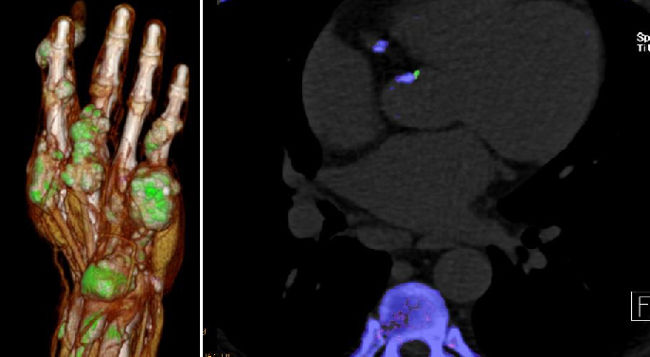

- Dual-energy CT (DECT) in gout: comparison with US, findings in extra-articular regions and cardio in gout and subgroup patients

- X-ray in comparison with DECT in gout patients

Musculoskeletal Imaging

- Klauser AS, Halpern EJ, Strobl S, Gruber J, Feuchtner G, Bellmann-Weiler R, Weiss G, Stofferin H, Jaschke W.: Dual-Energy Computed Tomography Detection of Cardiovascular Monosodium Urate Deposits in Patients With Gout. JAMA Cardiol. 2019 Oct 1;4(10):1019-1028.

- Strobl S, Kremser C, Taljanovic M, Gruber J, Stofferin H, Bellmann-Weiler R, Klauser AS.: Impact of Dual-Energy CT Postprocessing Protocol for the Detection of Gouty Arthritis and Quantification of Tophi in Patients Presenting With Podagra: Comparison With Ultrasound. AJR Am J Roentgenol. 2019 Dec;213(6):1315-1323.